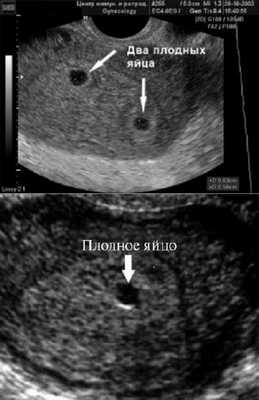

Фото УЗИ плода при беременности 4-5 недель

Самый ранний срок, на котором можно разглядеть с помощью трансвагинального УЗИ плодное яйцо в полости матки - это 30-й день гестации, или 4-5 акушерских недель беременности. Уровень ХГЧ крови при этом должен быть не менее 1000 мЕд/мл. В это время ещё не видно ни эмбриона, ни желточного мешка. При визуализации двух плодных яиц можно утверждать, что это дихориальная многоплодная беременность. При визуализации одного плодного яйца можно утверждать, что это монохориальная беременность. Но на этом сроке мы ещё не можем сказать сколько эмбрионов находится в каждом плодном яйце. Кроме того, во время однократного УЗИ мы ещё не можем сказать, прогрессирует ли данная беременность, так как у эмбриона ещё нет сердцебиения. Средний внутренний диаметр (СВД) плодного яйца на этом сроке 2-10 мм.

В заключении будет указано: Маточная беременность малого срока.